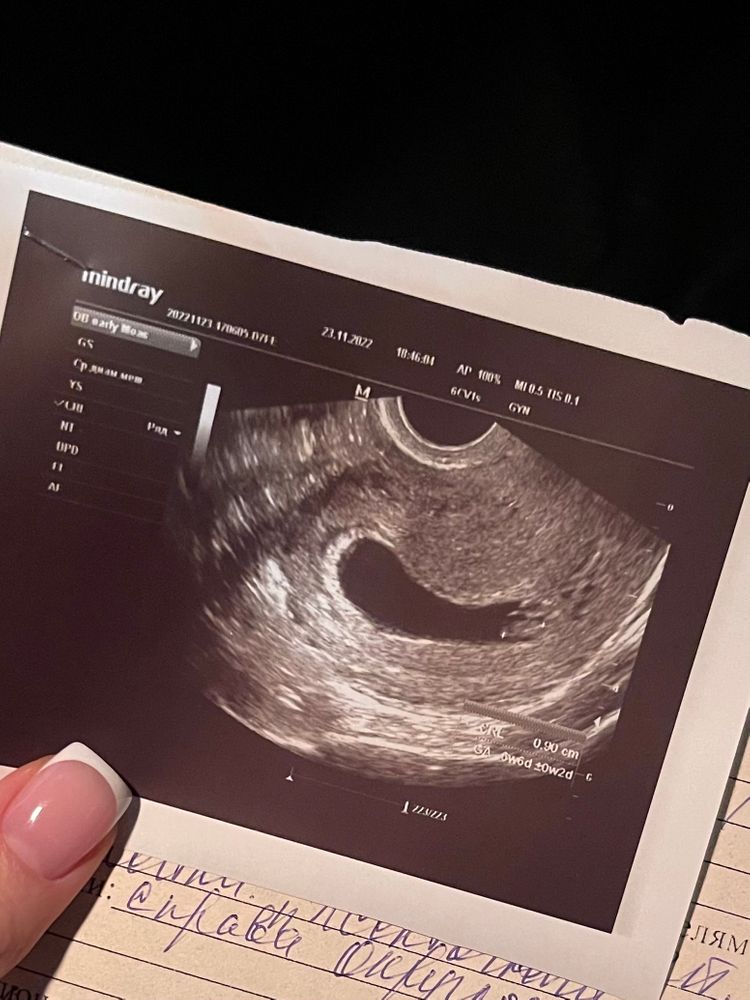

Узи 5 недель

Сходила на узи еще сегодня, говорит вроде как беременность есть, хотя и так знаю, по тестам видно, есть плодное яйцо, эмбриона пока не видно, но говорит это нормально для маленького срока. По м. сегодня 5 недель и 1 д, эмбр.3 недели и 3 д. Это по моему календарю. Бумажку узист не распечатывала, так толком тоже ничего не сказала, рекомендовала пройти в городе узи на совр аппарате. Но так я краем уха услышала 8,3, это скорее всего как я поняла, размер Пя? Ну потом добавила что-то типа"3-4", это вроде как недели эмбр. Так вот, размер пя совпадает ли сроку?

Поробуйте в другом месте переделать. Сегодня делала. Все бумаги дали. Ну у меня срок чуть по больше 6 недель 4 дня. По узи 6 недель ровно написали. Уже сердцебиение слышно.